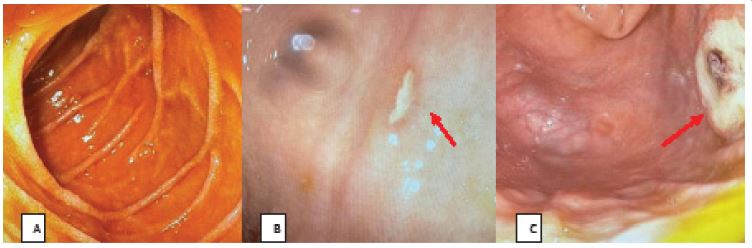

The patient, a 71-year-old male with a BMI of 23.4 kg/m2, underwent a gastroscopy on March 9, 2023, which revealed a cardia mass. Pathology confirmed adenocarcinoma. Preoperative thoracoabdominal Computed Tomography (CT) showed intact bilateral pleura without thickening, no pleural effusion, and an intact diaphragm (Figures 1A & 1B). On March 6, 2023, he underwent a laparoscopic radical total gastrectomy, D2 lymph node dissection, and esophagojejunostomy with Roux-en-Y reconstruction at our hospital. Histopathology revealed moderately to poorly differentiated gastric adenocarcinoma G3, with tumor staging of ypT3, ypN0 (0/22), L0, V0, R0, cM0. On postoperative day 17, a follow-up thoracoabdominal CT showed localized thickening of the bilateral pleura, a small amount of right pleural effusion, and the esophagojejunostomy located within the thoracic cavity (Figures 1C & 1D). The patient was discharged cured and received adjuvant chemotherapy thereafter.

Figure 1: Preoperative and postoperative thoracoabdominal CT scans of the patient who underwent laparoscopic total gastrectomy.

A-B. Preoperative images; C-D. Postoperative images.